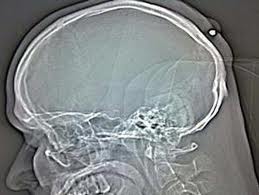

Unik tapi Nyata -Seorang pria asal Jerman hidup normal dan baik-baik saja selama lima tahun tanpa dia sadari bahwa dia telah tertembak dan peluru kaliber 0,22 bersarang dikepalanya. Hal itu baru dia ketahui ketika dia pergi ke dokter, karena dia berpikir dia memiliki kista.

Karena kondisinya yang sangat mabuk, pria tersebut tidak tahu apa yang telah terjadi pada dirinya. Yang dia ingat hanyalah bahwa dia telah mendapatkan pukulan di kepala sekitar tengah malam saat pesta Tahun Baru "di tahun 2004, atau 2005"